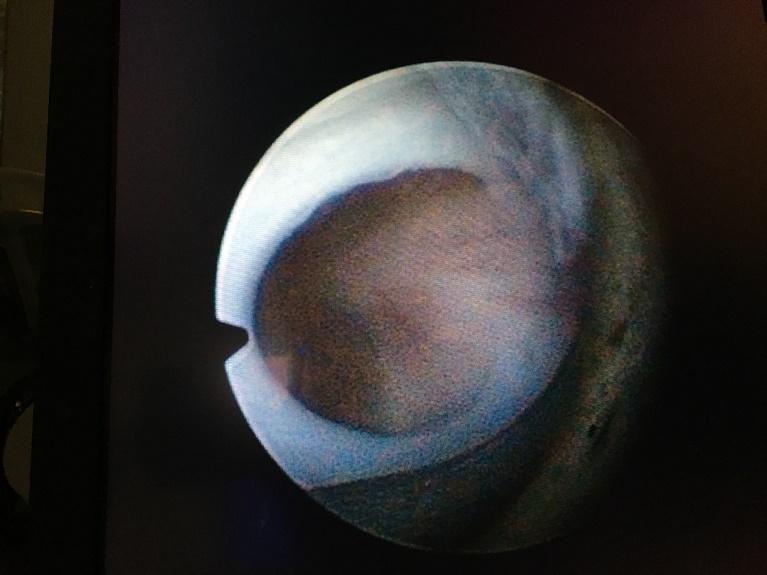

Beeld van urethrakleppen bij de kijkoperatie (cystoscopie). De vliezen zitten vast aan de boden en zijwand van de plasbuis en zijn aan het “plafond” van de plasbuis samengegroeid.

Als de nierfunctie en de situatie van uw zoon zijn gestabiliseerd kunnen de kleppen worden behandeld middels een kijkoperatie via de plasbuis. Meestal wordt dat een tot twee weken na de geboorte gedaan. Als uw zoon zeer vroegtijdig is geboren moet er enkele weken worden gewacht tot hij is gegroeid. Voor de operatie wordt uw zoon onder narcose gebracht. Dit zal gedaan worden door een anesthesioloog die gespecialiseerd is in de behandeling van kinderen. U mag met uw zoon mee naar de operatiekamer. Als hij slaapt, wacht u op de verpleegafdeling tot de operatie klaar is. Het is geen zware operatie en het duurt ongeveer 30 minuten. Met de voorbereiding voor de operatie, het wakker maken nadien en vervoer naar de uitslaapkamer, kan het zijn dat u pas na 1,5 tot 2 uur naar hem toe mag. Soms wordt ervoor gekozen om het kind wakker te laten worden op de kinder intensive care. Meestal verblijft het kind daar maar één nacht.

Tijdens de operatie worden, via een kijkertje met een camera, in de plasbuis de kleppen ingesneden zodat ze niet meer kunnen opbollen tijdens het plassen. Soms ook wordt een nauwe gespierde blaasuitgang wijder gemaakt. Er ontstaan kleine wondjes aan de binnenkant van de plasbuis, aan de buitenkant is daar niets van te zien. Uw zoon krijgt tijdens de operatie opnieuw een blaaskatheter. Door de wondjes kan de urine in de opvangzak rood kleuren en kan er ook bloed naast de katheter uit het plasgaatje komen. Gelukkig houdt het bloeden snel op. Kort na de operatie, vaak de volgende dag, kan de katheter worden verwijderd. Uw zoon moet nu “op eigen kracht” plassen. Een tot enkele dagen na het verwijderen van de katheter zal de nierfunctie weer worden gecontroleerd en zal opnieuw echografisch onderzoek worden gedaan. Als deze onderzoeken goede resultaten laten zien en het gaat goed met uw zoon, mag hij met ontslag.